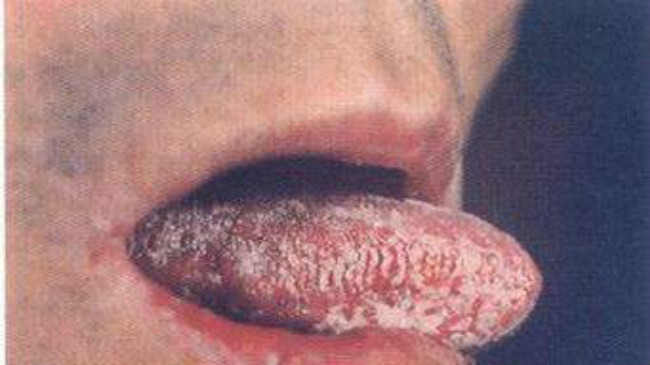

嘴唇白色念珠菌感染

舌頭白色念珠菌感染

口腔內白色念珠菌感染